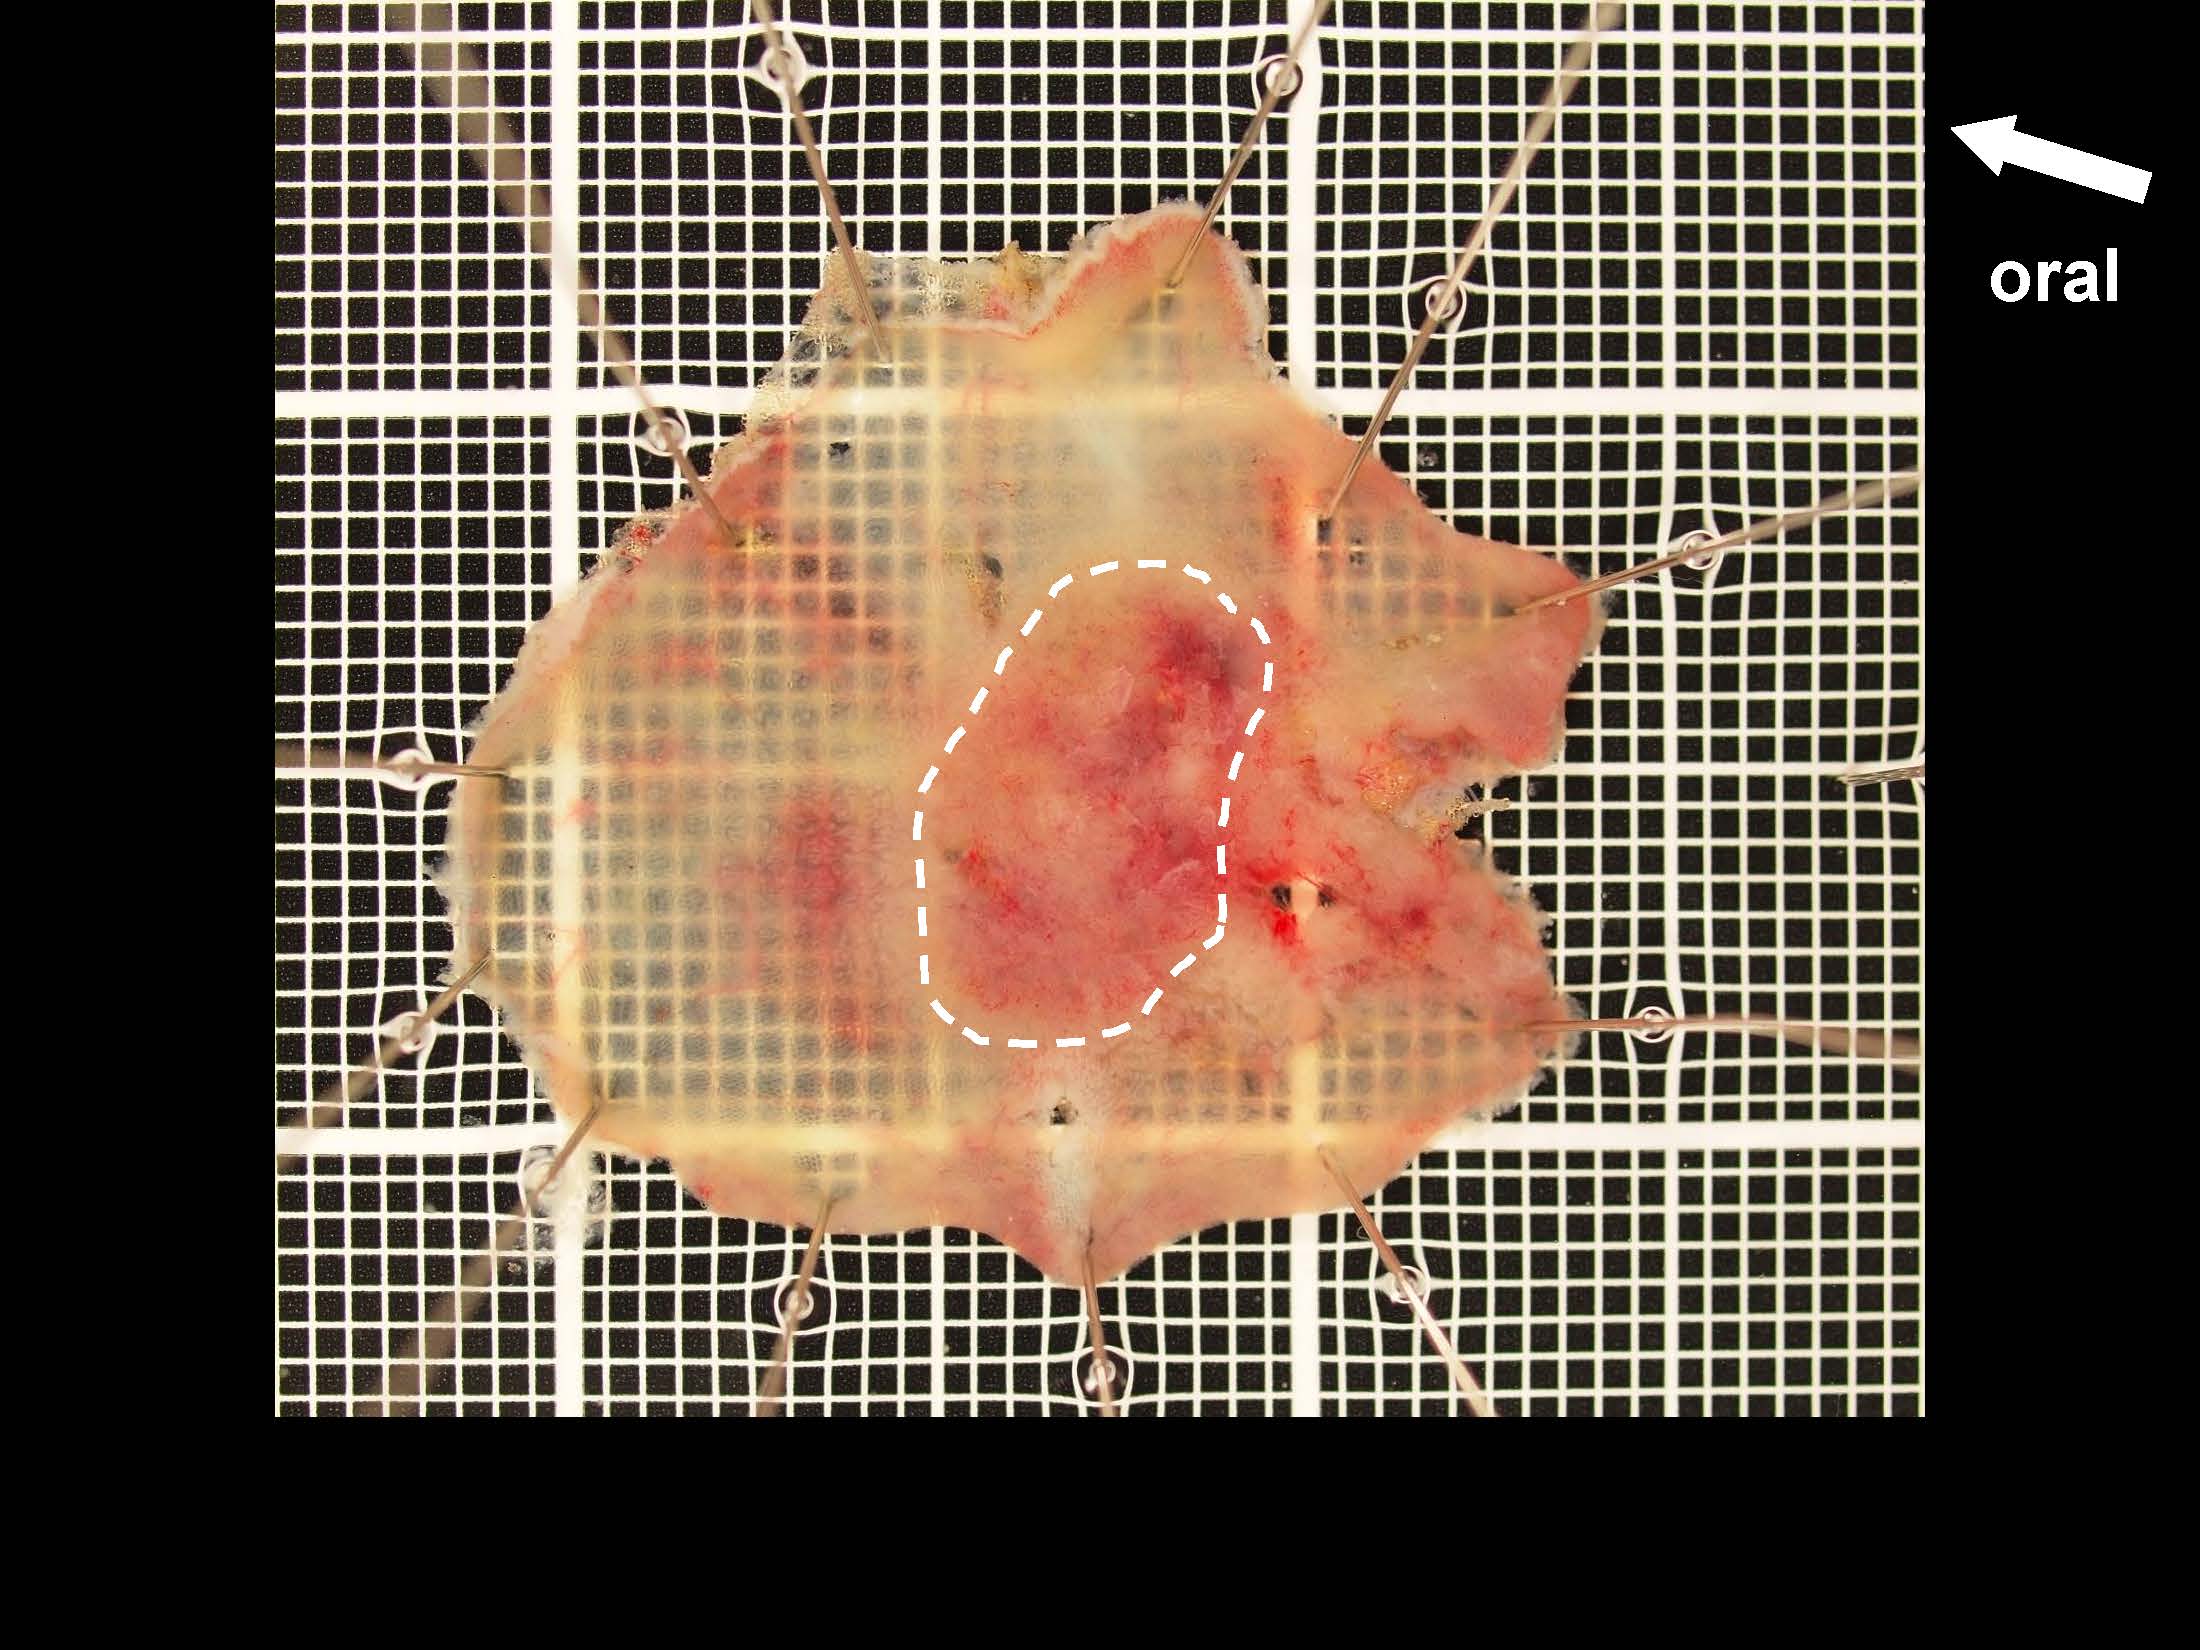

消化管Mapping~大腸~ 2021.10.27

消化管Mapping~大腸~

消化管Mapping

全ページPDFのダウンロードはこちら